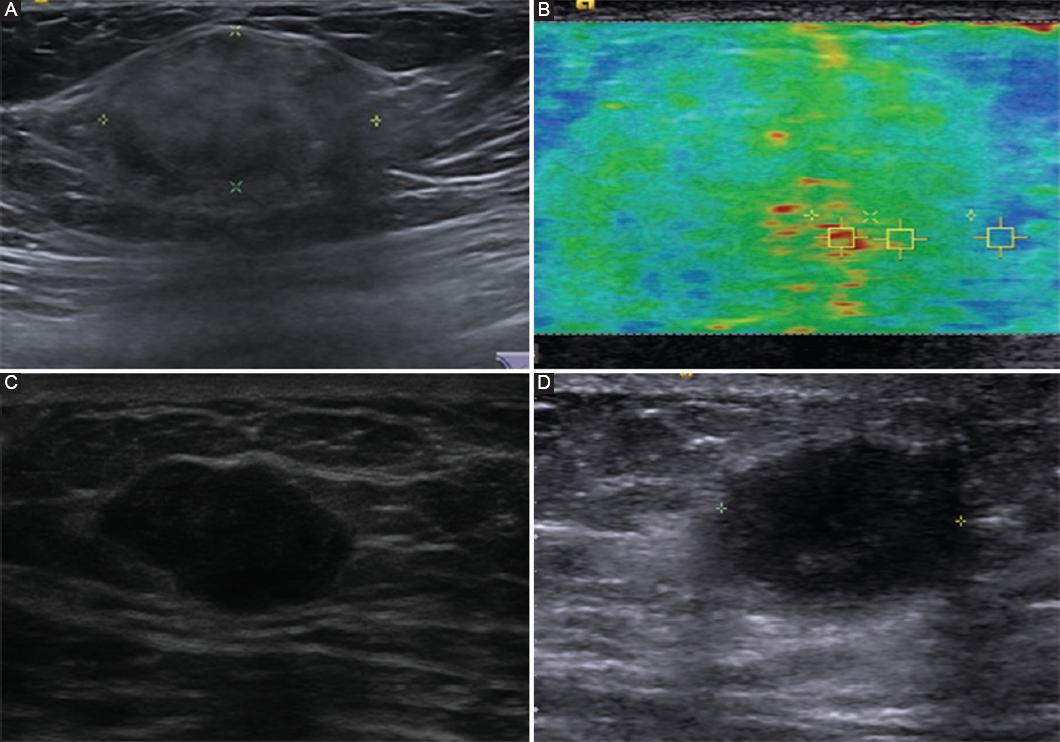

Figura 4 Características ultrasonográficas y por elastografía de lesiones benignas de mama en los hombres. A: ultrasonido que muestra una lesión con características de nódulo isoecoico con bordes bien delimitados. El reporte histopatológico fue compatible con un miofibroblastoma. B: elastografía que muestra la solidez del tejido, el cual fue auxiliar para integrar el diagnóstico junto al reporte histopatológico final que indicó un miofibroblastoma. C: ultrasonido que muestra una lesión en la mama con características de nódulo hipoecoico con bordes irregulares, más ancho que alto, el cual resultó ser un fibroadenoma. D: ultrasonido que muestra una lesión en la mama, con presencia de un nódulo hipoecoico de bordes bien delimitados, cuyo estudio histopatológico reportó como fibroadenoma.